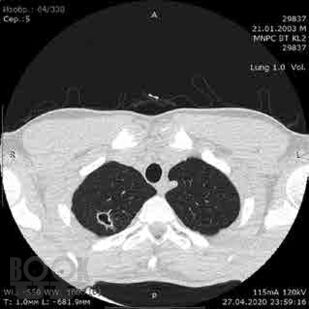

Сборник включает вызвавшие наибольший интерес аудитории лекции и доклады на различных научно-практических конференциях в 2019–2020 гг. по актуальным проблемам пульмонологии и аллергологии детского возраста, таким как: современные методы диагностики и лечения, острые и хронические инфекционно-воспалительные и аллергические заболевания органов дыхания, муковисцидоз, туберкулез органов дыхания, Covid-19, а также страницы истории, различные другие информационные материалы. Ежегодник адресован практикующим детским пульмонологам и аллергологам.